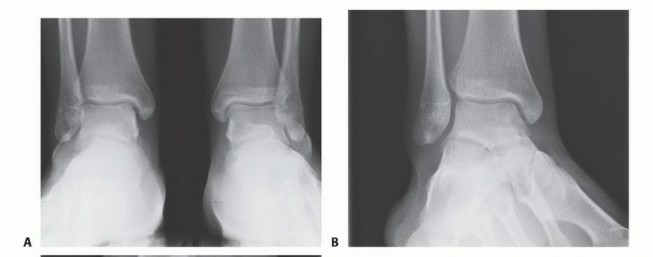

DEFINITION Lateral ligament instability occurs in some patients after an inversion injury.38 Although an inve…

DEFINITION There are several reasons for cartilaginous defects of the ankle: Traumatic injury Osteochondritis…

DEFINITION Medium-sized osteochondral defects of the talar dome May approach the talar shoulder (transition o…

DEFINITION Because of their nature and deep location, posterior ankle problems pose a diagnostic and therapeu…